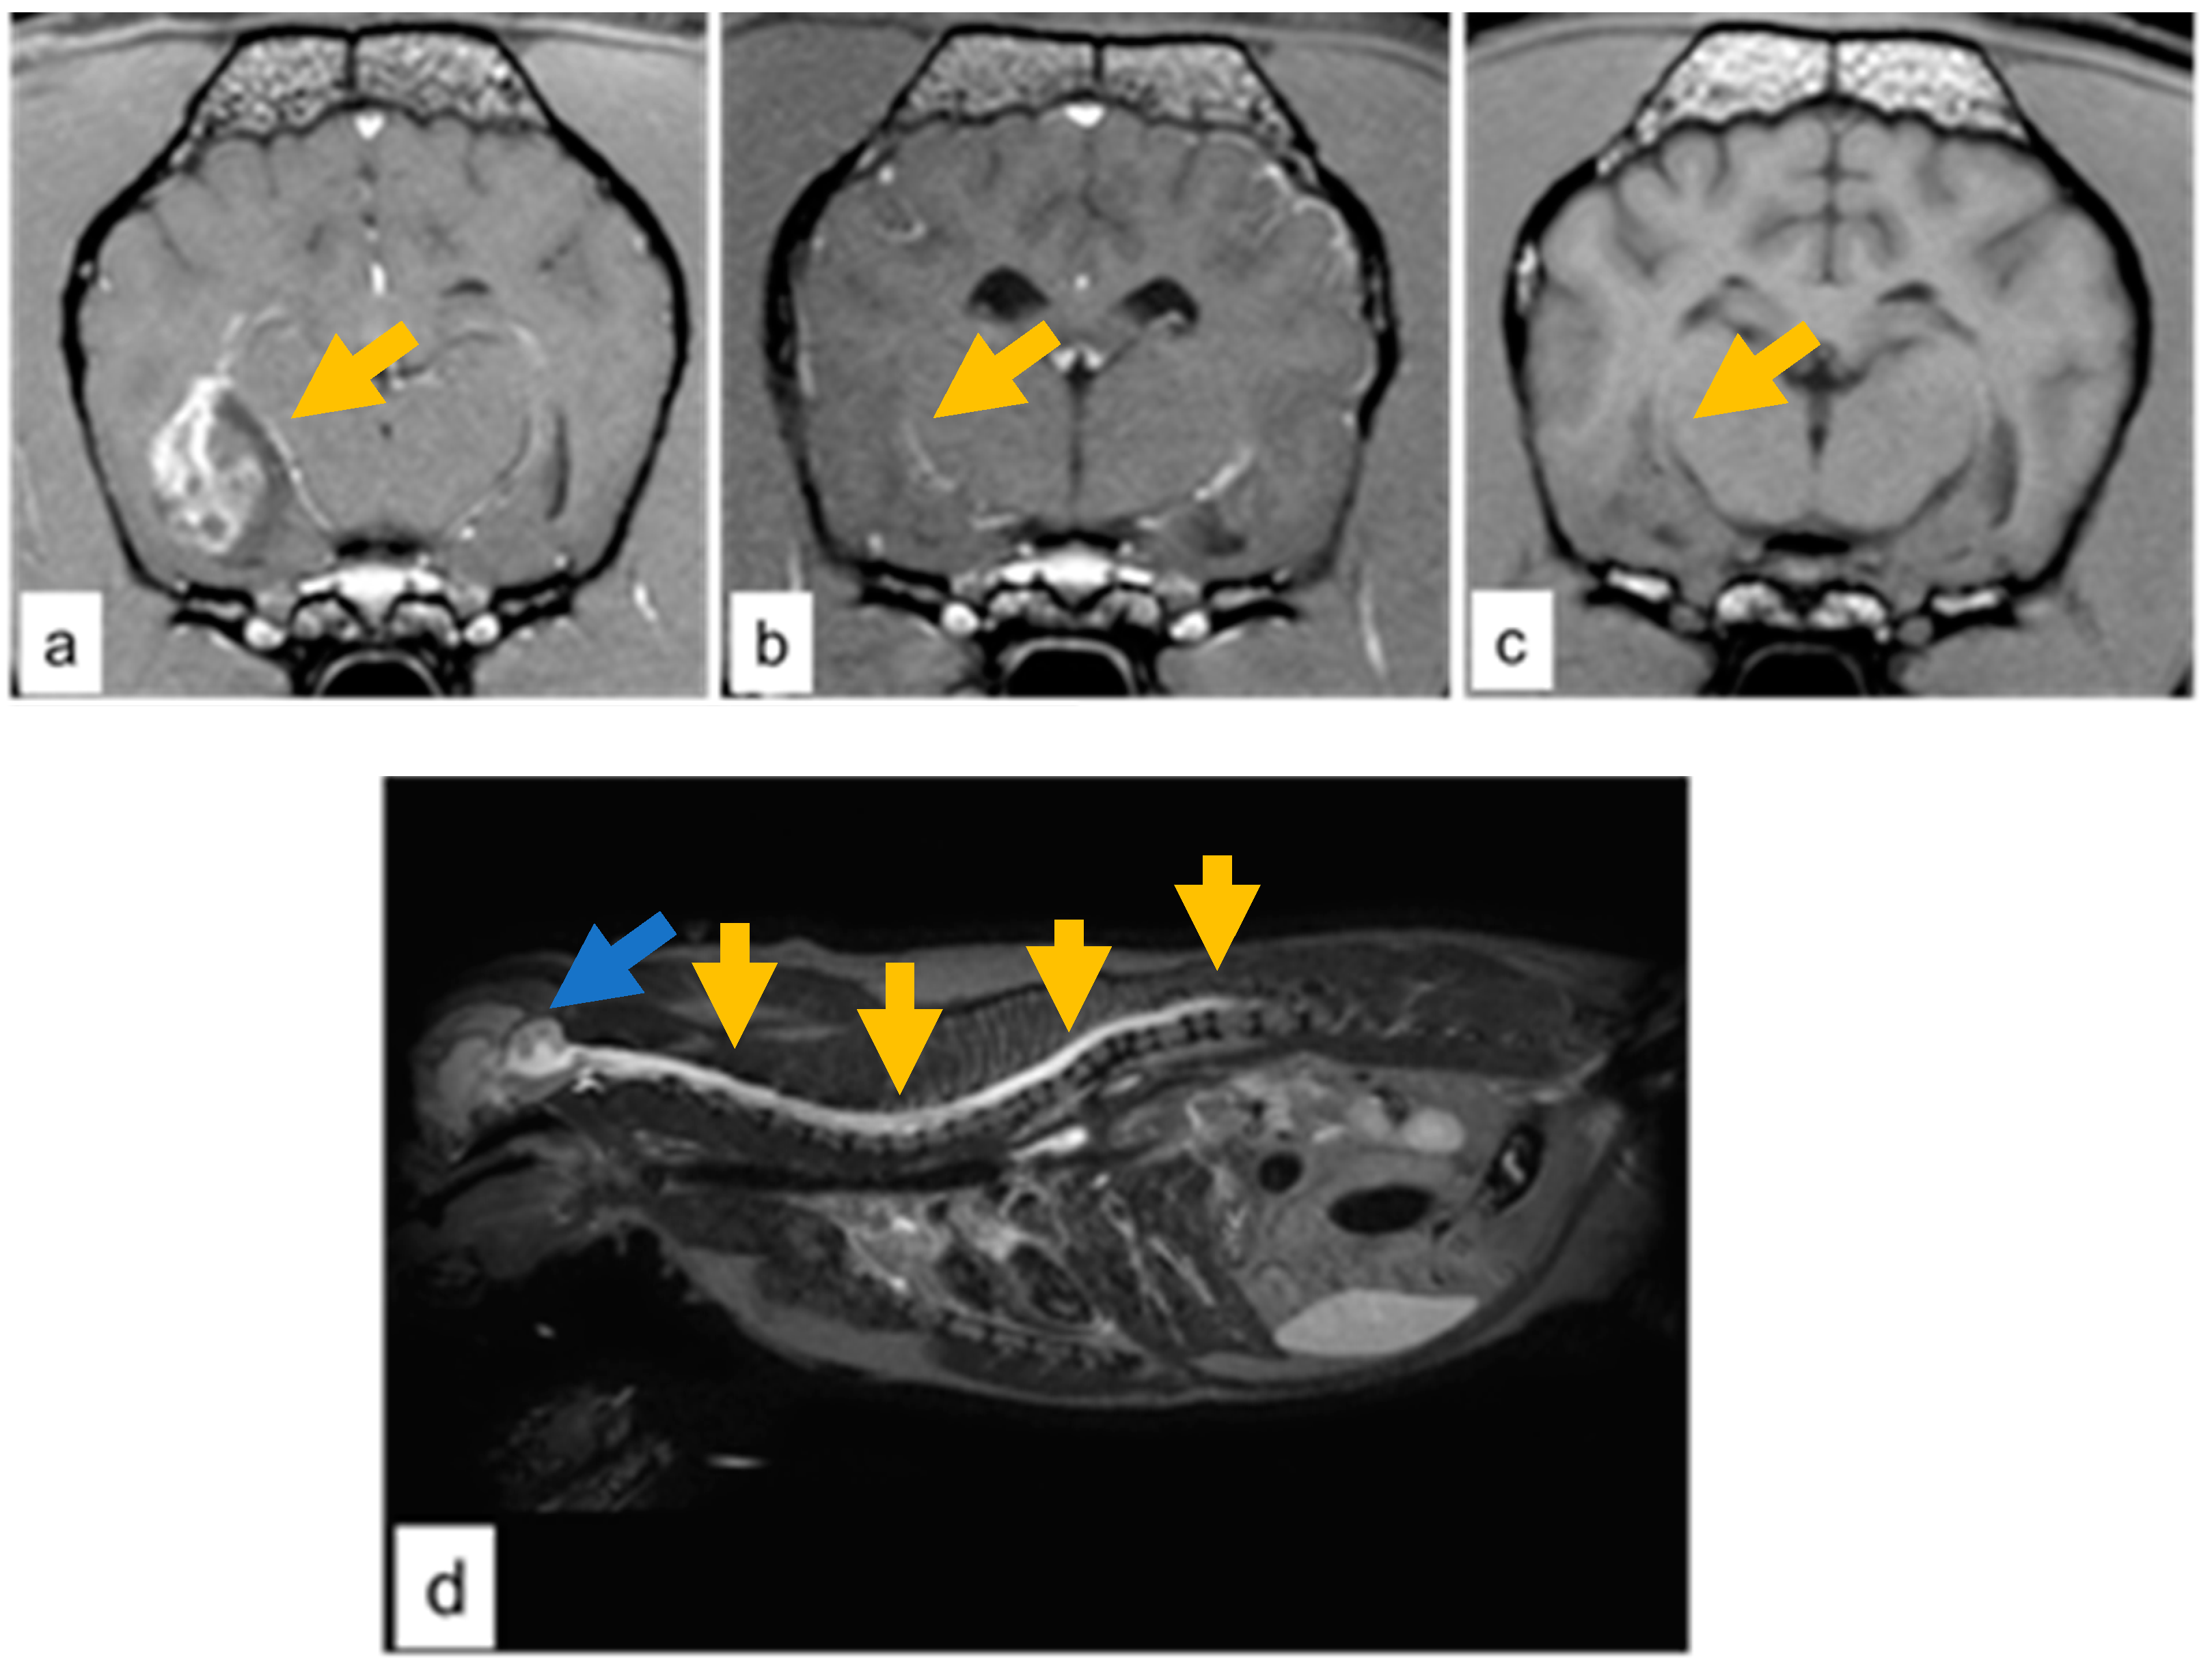

Cases 3 and 4 presented a large temporo-paraventricular grade IV presumed glioma with necrosis, hemorrhage, and cystic regions with contrast enhancement in case 3 (Figure 1a). Two months after the radiotherapy course, both dogs had a near-complete response with no sign of recurrence and no contrast enhancement (Figure 1b).

Figure 1.

Case 3, grade IV glioma (a) T1-W image with contrast enhancement showing a well-demarcated tumor at the temporal-paraventricular region (dark-yellow arrow). (b) Two months post RT near-complete regression was observed (dark-yellow arrow). (c) Six months post RT, hypointense lesion consistent with a gliotic scar at the temporal-paraventricular region (dark-yellow arrow). (d) Case 4, grade IV glioma; cervical and thoracic involvement of the spinal cord on T2-W image by the hyperintensity signal (dark-yellow arrow). and with concomitant enlargement of the fourth ventricle (blue arrow).

In both cases, the neurological status improved to normal and seizures gradually subsided in terms of both severity and frequency. Consequently, the corticosteroid treatment was gradually tapered. Six months after RT, case 3 presented a residual gliotic scar at the primary tumor site (Figure 1c). Nine months after RT, the sagittal T2-W MRI showed the progression of the disease along the entire spinal cord (Figure 1d) with a hyperintensity signal evidenced in the cervical and thoracic tract of the spinal cord, which was swollen with a concomitant enlargement of the fourth ventricle and the central canal, and hyperintensity of the meninges. Cerebrospinal fluid (CSF) examination ruled out inflammatory processes and infections, and the presence of neoplastic cells was compatible with a cranio-spinal diffusion of the tumor.